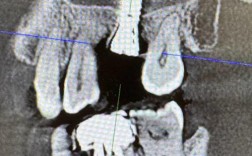

口腔检查与影像学评估:医生会通过视诊、探诊初步检查口腔状况,并拍摄曲面断层片、CBCT等影像学检查,观察牙槽骨的厚度、高度、密度,以及邻牙、下牙槽神经管、上颌窦等重要结构的位置,为洗牙和后续种牙方案提供依据。